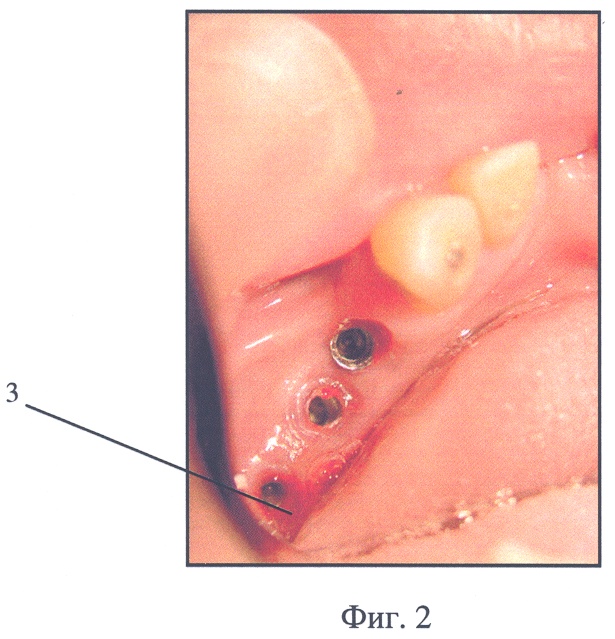

2. В указанный период в зону контакта десны и головки проникают пищевые остатки, бактериальная и грибковая флора. Инфицирование тканей приводит к их воспалению (3, фиг.2) и затягиванию сроков протезирования. Для предупреждения инфицирования больному предписывают санацию этих зон путем механического удаления пищевых остатков и дезинфицирующего полоскания. Монолитная непроницаемая структура устройства затрудняет эти действия.

Фиг.2. Воспаление десны вблизи десневого канала зубного имплантата (позиция 3).